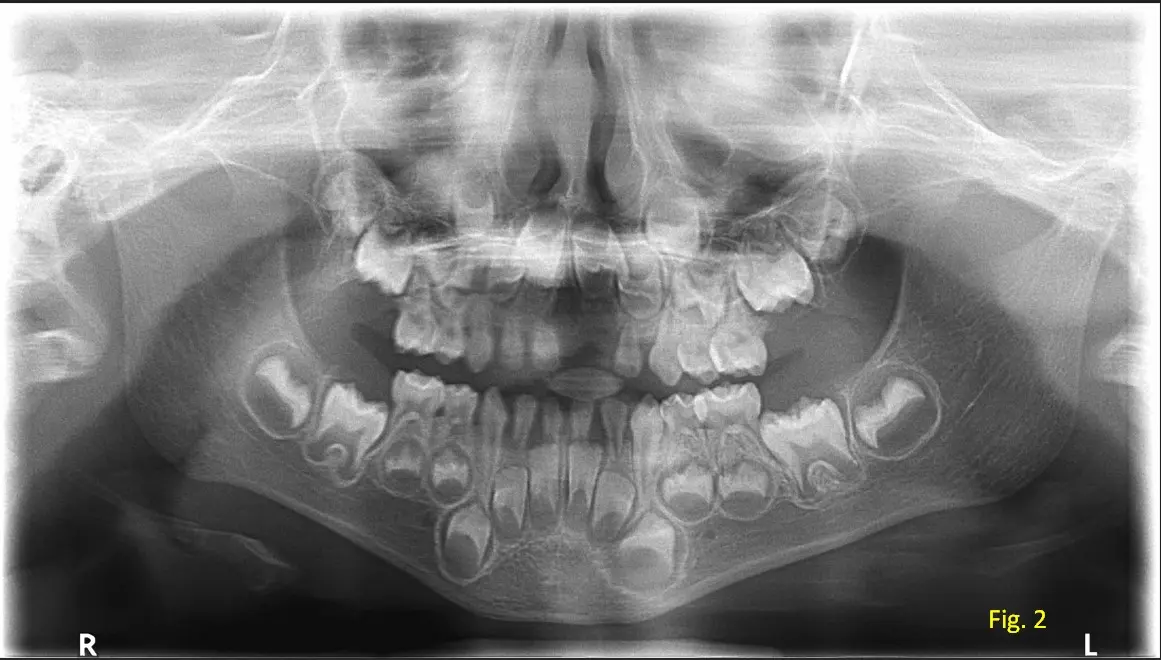

Al observar la radiografía panorámica, (ver figura 2) la odontóloga comenta que los dientes temporales, del paciente ya se encuentran próximos al recambio, dado que los gérmenes de los dientes permanentes están en proceso activo de erupción. Además, se evidencia espacios suficientes en las arcadas dentarias para permitir la erupción adecuada y alineada de los dientes permanentes definitivos, sin signos de apiñamiento o interferencias óseas.

La radiografía panorámica, aun en pacientes pediátricos, resulta una herramienta fundamental para el diagnostico post-trauma, ya que brinda una visión amplia y no invasiva del desarrollo dentario y estructuras adyacentes.

Su uso oportuno permitió un abordaje adecuado del caso y una planificación a futuro para el seguimiento del desarrollo dental del niño.